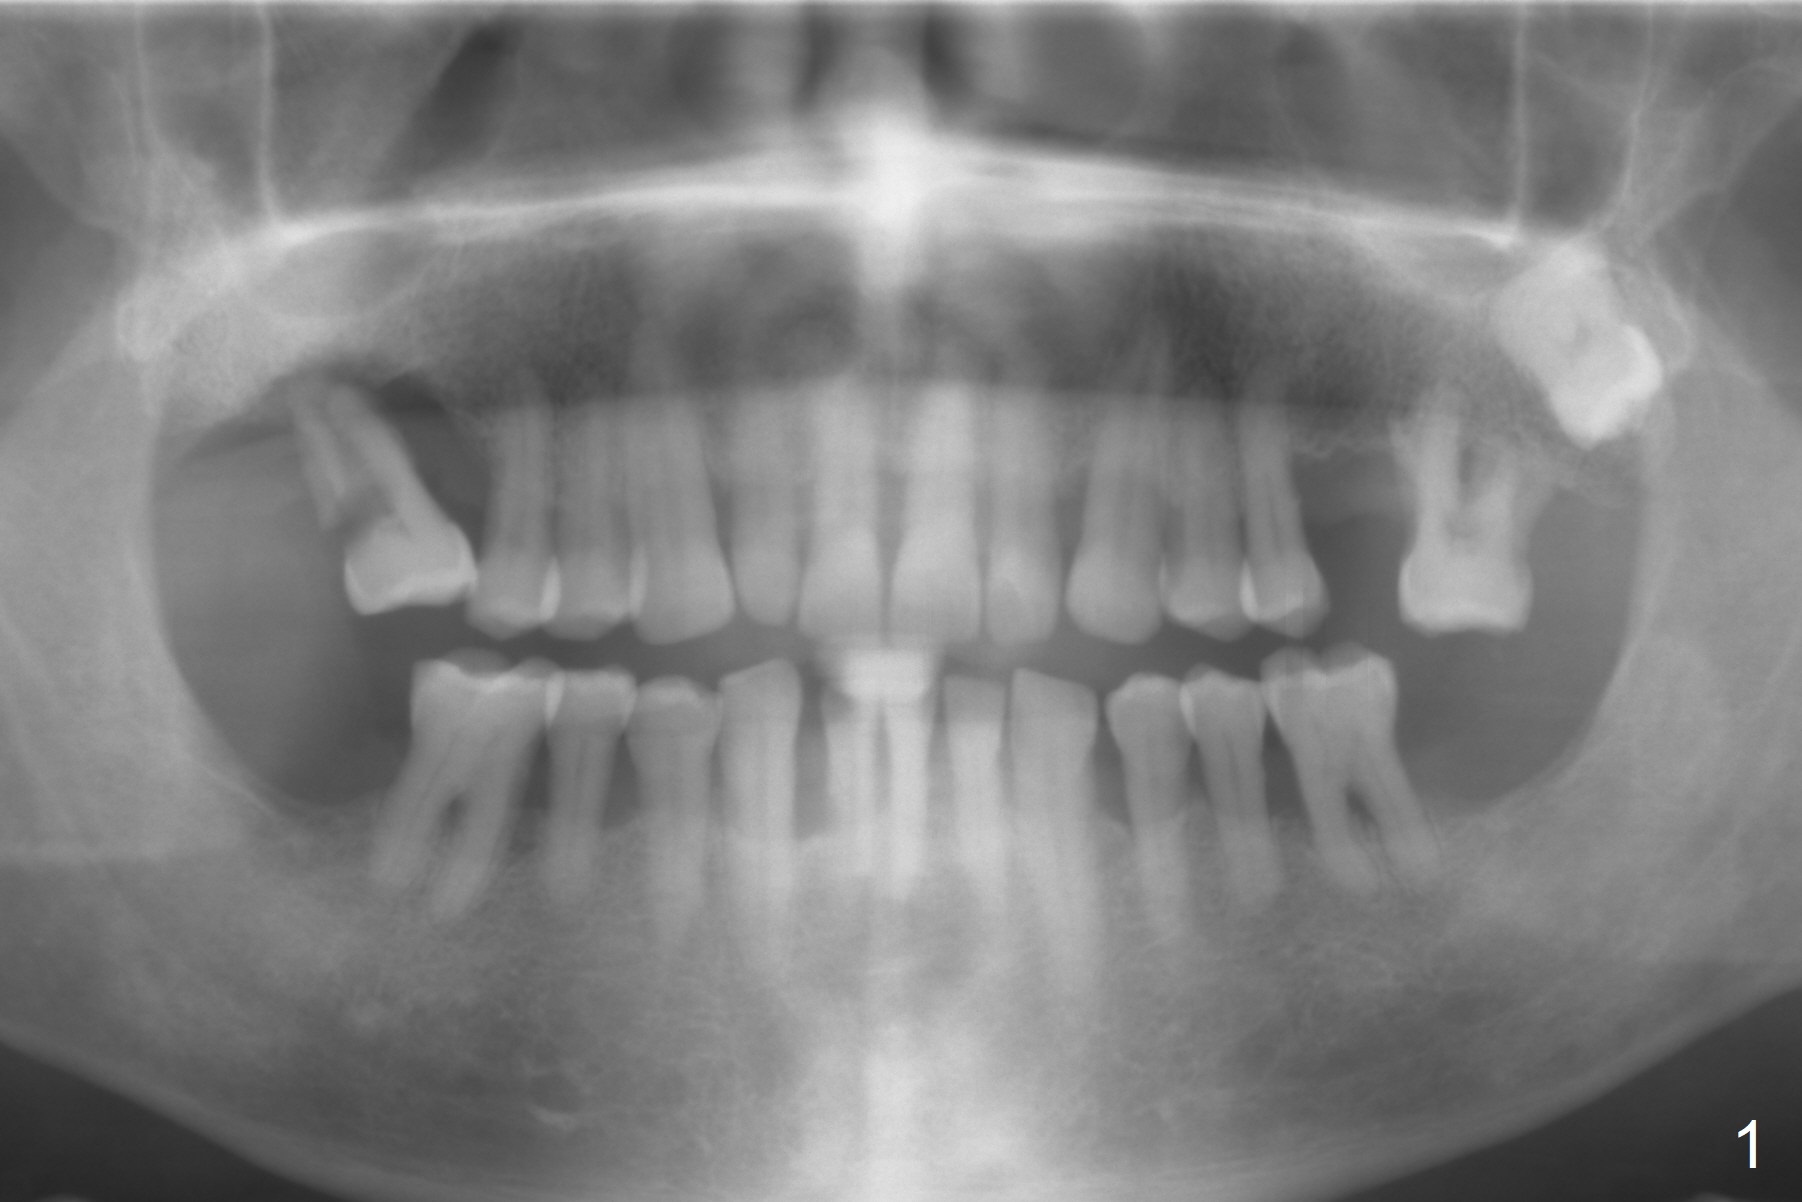

A 53-year-old man has severe peridontitis (Fig.1). The tooth #3 has exfoliated. The 1st implant will be placed at #3, where the gingiva seems to be thick (Fig.2: 10 mm). A mill abutment will be used.